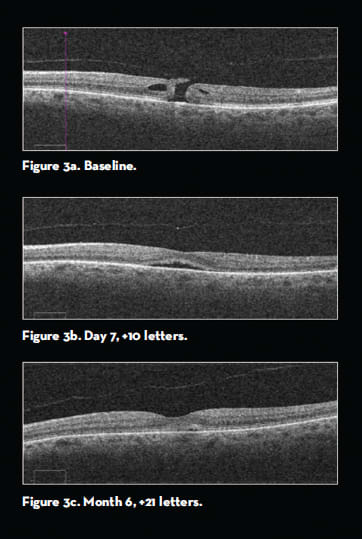

Subgroup analysis of eyes with full-thickness macular holes (FTMHs) showed closure in 40.6% of eyes following injection of ocriplasmin, compared with 17% of placebo eyes (P=.004) (Figure 3). Approximately 58% of the eyes with FTMHs <250 µm saw closure with ocriplasmin, compared with just 20% in the placebo eyes. Respectively, 76.7% and 51.2% of the eyes in the FTMH subset achieved ≥2- and ≥3-line improvements in visual acuity.

Figure 3. From the MIVI TRUST trial, macular hole.

A: OCT demonstrating evidence of a macular hole with visual acuity of 20/63.

B: OCT image seven days after intravitreal injection of ocriplasmin with a gain of 10 letters.

C: OCT image six months after intravitreal injection of ocriplasmin. Macular hole is closed with minimal subretinal fluid and a gain of 21 letters.